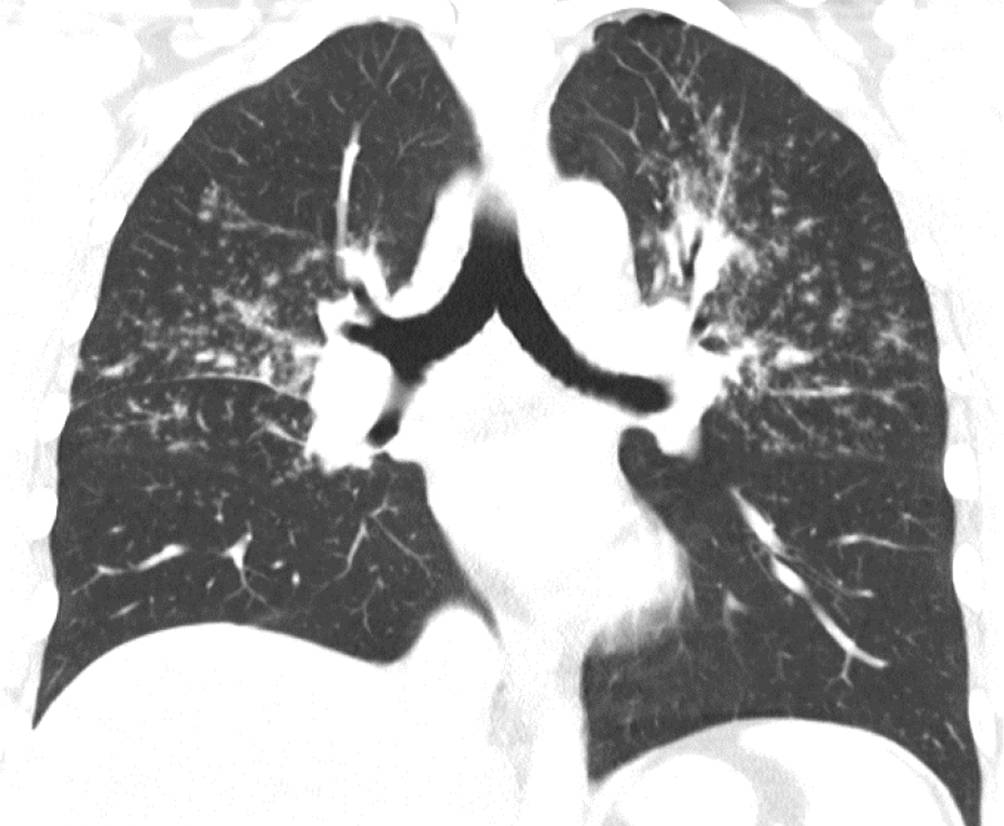

Vorwegzunehmen ist, dass die sichere Diagnose der Sarkoidose einen histologischen Nachweis der granulomatösen Entzündung und den Ausschluss anderer Ursachen von Granulomen, beispielsweise Tuberkulose oder Vaskulitiden, erfordert. Hilfreich dabei ist die Bildgebung: Während die Thoraxröntgenuntersuchung zwar durch die mediastinale und hiläre Lymphadenopathie und Parenchymveränderungen (Abb. 2) auffällig sein kann, ist die Computertomographie des Thorax (CT) wesentlich genauer und kann auch geringere Krankheitsausprägungen sicher detektieren (Abb. 3). Die 18F‑FDG-PET/CT hat sich weiters bewährt, extrathorakalen Befall darzustellen, geeignete Biopsiestellen zu identifizieren und in komplexen Fällen das Krankheitsansprechen zu kontrollieren (Abb. 4).

Abb. 3

Schnitt aus einer Computertomographie eines Sarkoidosepatienten. Es zeigen sich klassische perilymphatisch angeordnete Noduli, die durch Beteiligung der Septen und der Pleura auffallen. Im linken Oberfeld konfluieren sie zu einem dichteren Infiltrat